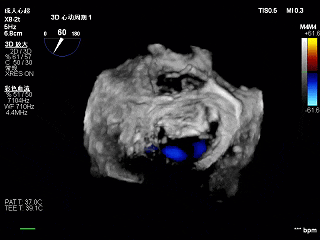

3D-ZOOM 彩色多普勒显示反流主要来源于2区